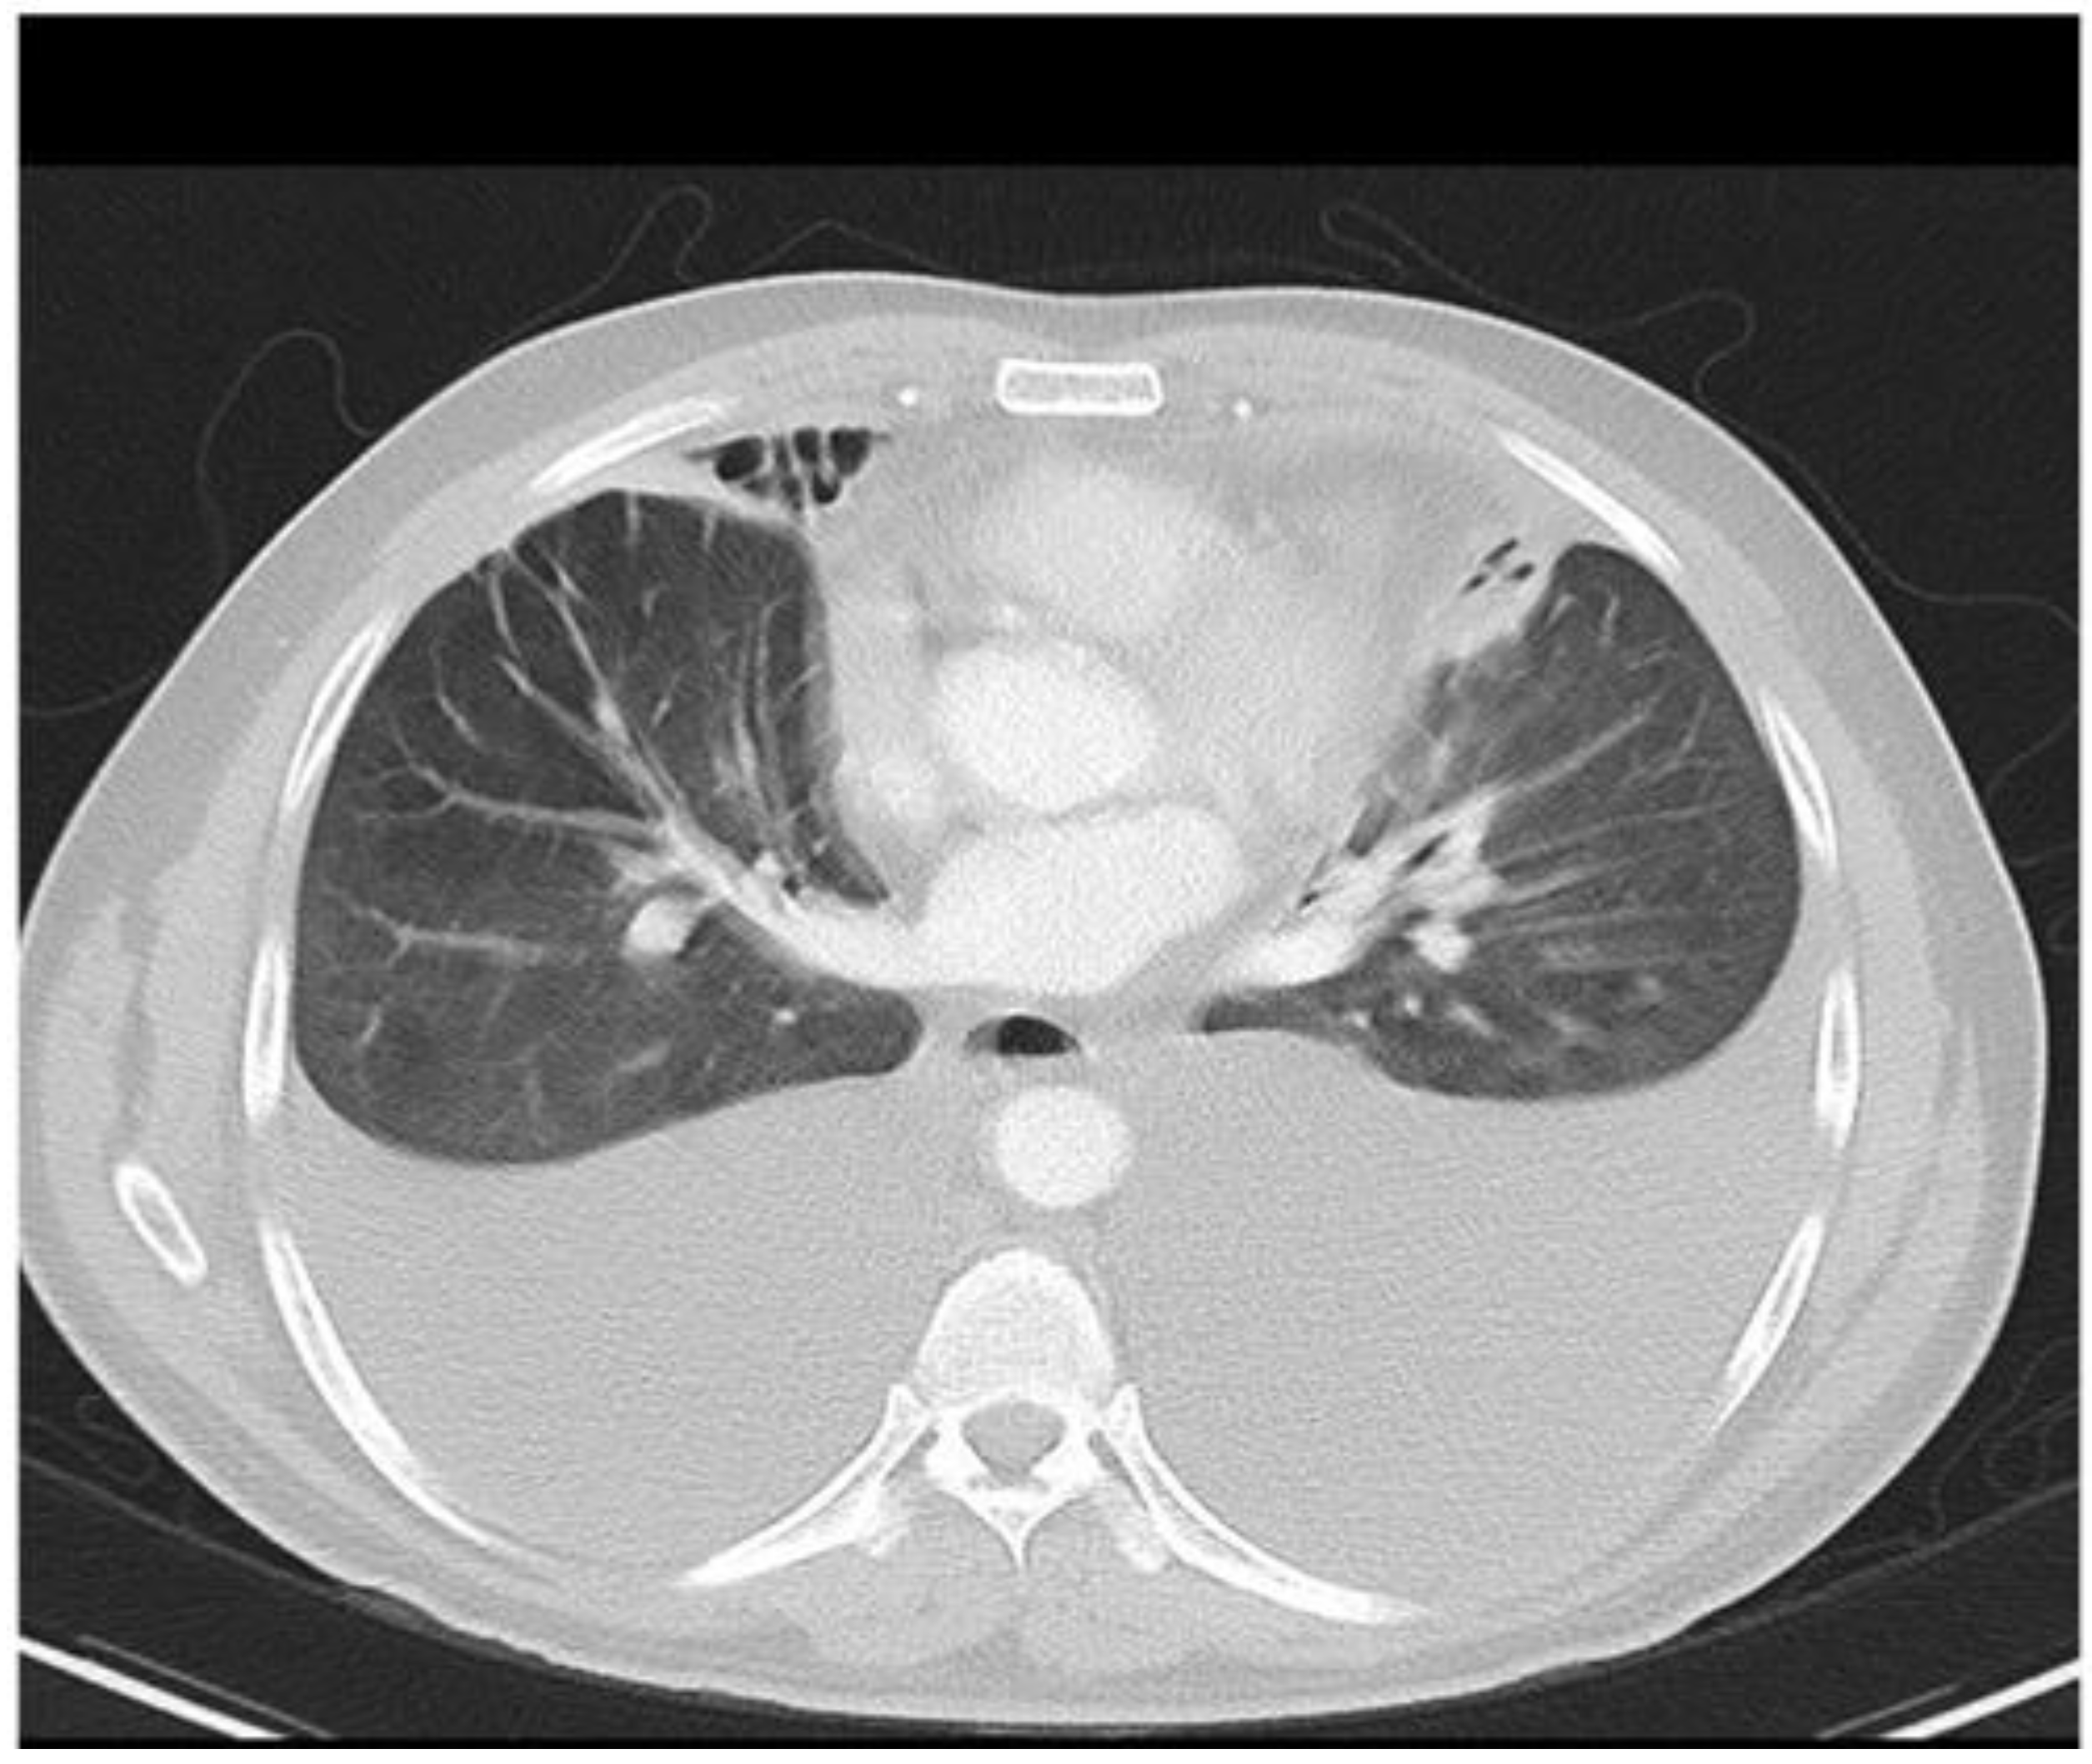

2.3.2. Computed Tomography